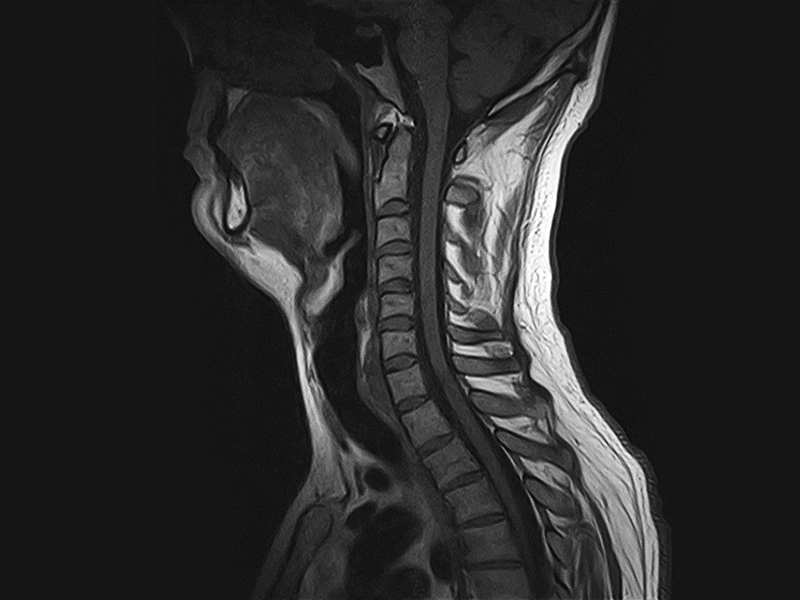

Klinické snímky